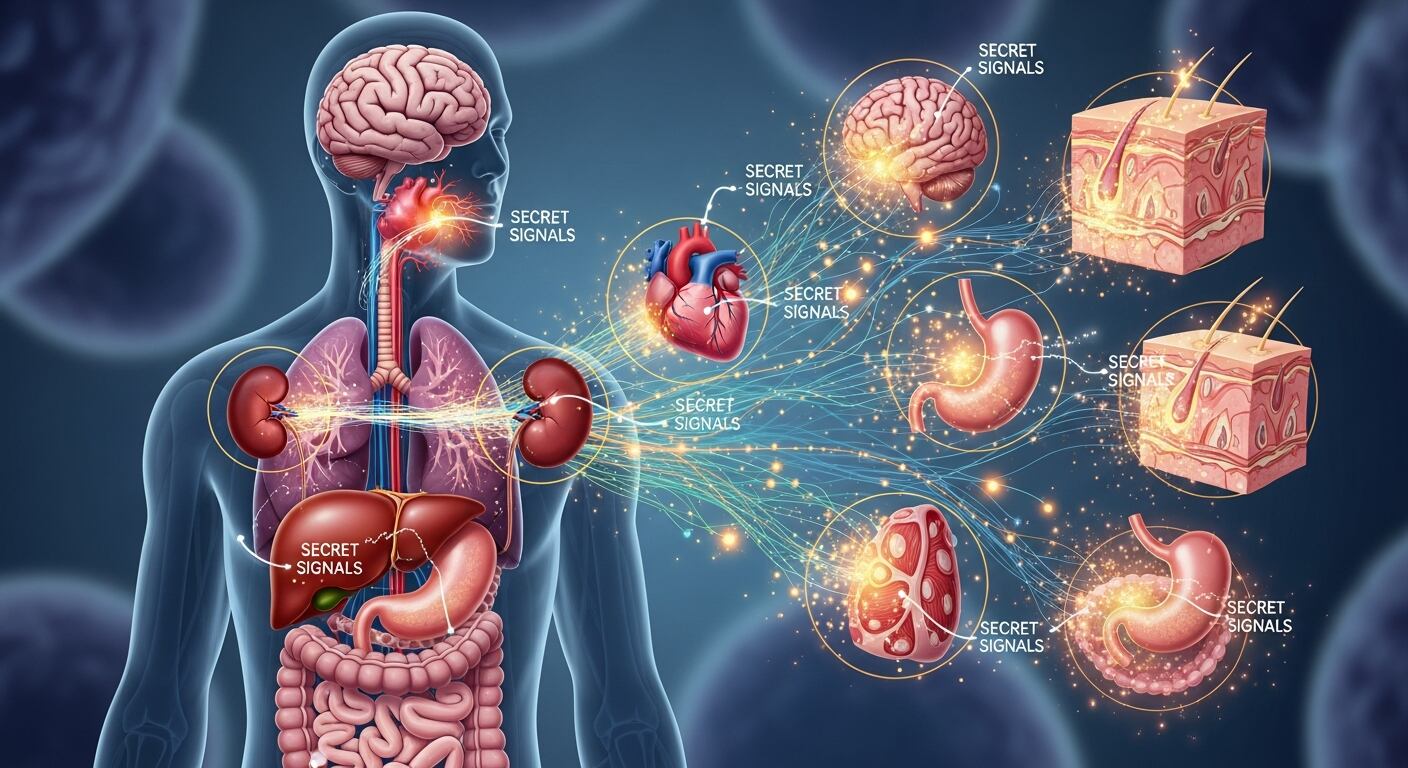

El cuerpo humano es un entramado de conexiones invisibles que, hasta hace poco, permanecían ocultas incluso para la ciencia. Hoy, el descubrimiento de la comunicación interorgánica está revolucionando la manera en que entendemos la salud, el envejecimiento y la regeneración de los tejidos. Aprovechar estos sistemas podría abrir la puerta a tratamientos radicalmente nuevos y prolongar la vida en formas antes impensables.

Este hallazgo ha impulsado el surgimiento de un nuevo campo de estudio: la comunicación entre órganos, que retoma la antigua idea de que los órganos funcionan como un solo sistema integrado. Tradicionalmente, se consideraba que la información viajaba solo a través de nervios y hormonas, pero las investigaciones recientes muestran una variedad creciente de vías de comunicación, muchas de ellas desconocidas hasta ahora. “Creo que de repente veremos que los órganos se comunican de maneras que desconocíamos. Y si lo descubrimos, podremos ver qué falla en la enfermedad”, afirma Irene Miguel-Aliaga, del Instituto Crick de Londres.

La diversidad de lenguajes utilizados en la comunicación interorgánica es asombrosa. Además de las clásicas hormonas y señales nerviosas, los órganos emplean metabolitos, pequeñas moléculas y nuevas sustancias liberadas durante la contracción muscular que influyen en tejidos distantes. Este panorama se complejiza aún más con el descubrimiento de las vesículas extracelulares (VE), diminutas burbujas liberadas por las células que transportan proteínas, fragmentos de ARN y hasta mitocondrias, funcionando como auténticos mensajeros de información.